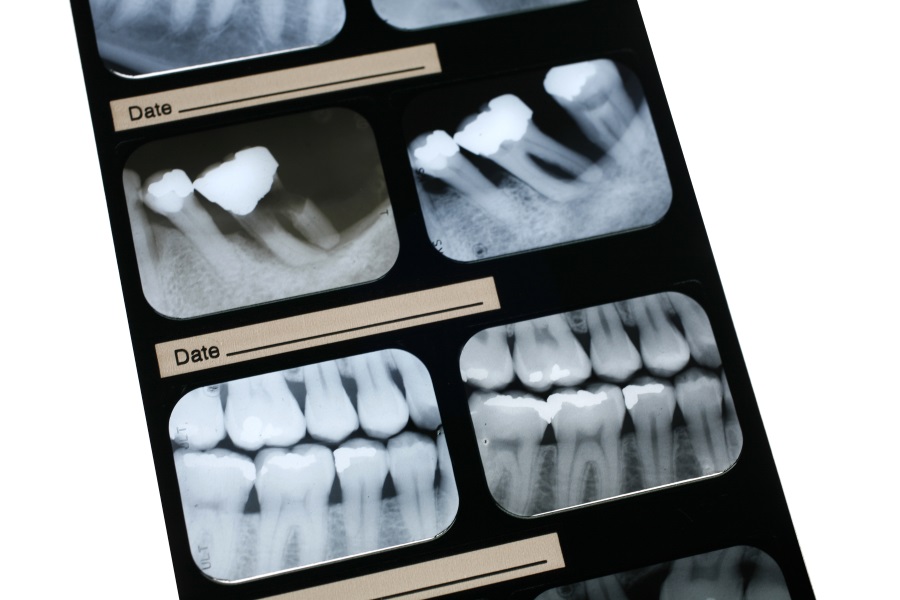

La Periodoncia es la rama de la odontologia se refiere al estudio y tratamiento de todos los problemas de las encías y el hueso que sostiene los dientes. Cada diente está enclavado en el hueso, unido fuertemente por una serie de estructuras que garantizan su fortaleza y correcto funcionamiento.

En ocasiones, las estructuras que rodean y soportan al diente (encías y hueso), pueden verse afectadas y si no se tratan a tiempo, podemos llegar a perder nuestra dentadura. Nuestros profesionales, pueden detectar las diferentes fases de este proceso y ayudar a corregirlas. Este proceso se denomina periodontitis, y es conocido vulgarmente como “piorrea”.